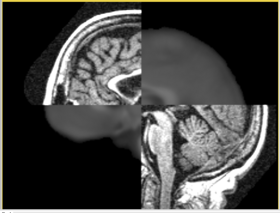

In this short tutorial, we will show how the Affine Registration module can be used to register two images from different subjects. The data is from the Oasis Brains project and the [http://www.loni.ucla.edu/Atlases/Atlas_Detail.jsp?atlas_id=6 ICBM. We will be registering the volumes icbm452_atlas_air12_sinc.hdr and OAS1_0001_MR1_mpr-1_anon.hdr. Be sure to load the volumes with the "Centered" option checked. Rotation is performed around the center, and a centered volume usually produces a more robust result.

In this short tutorial, we will show how the Affine Registration module can be used to register two images from different subjects. The data is from the Oasis Brains project and the [http://www.loni.ucla.edu/Atlases/Atlas_Detail.jsp?atlas_id=6 ICBM. We will be registering the volumes icbm452_atlas_air12_sinc.hdr and OAS1_0001_MR1_mpr-1_anon.hdr. Be sure to load the volumes with the "Centered" option checked. Rotation is performed around the center, and a centered volume usually produces a more robust result.